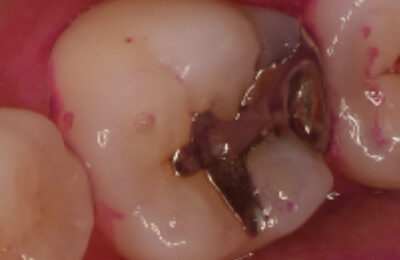

歯髄温存療法症例

術前

治療中

顕微鏡下でむし歯を除去

術後

レジン充鎮

矢印部に深いむし歯

封鎖性が良く、

組織の再生を促す

MTAセメントを充填 -

術後2年経過良好

| 主訴 | 冷たいものがしみる。 |

|---|---|

| 治療期間 | 歯髄温存療法1回 ダイレクトボンディング1回 |

| 治療費 |

|

| 治療内容 | マイクロスコープ下でむし歯の除去と、断髄(感染した死神経の一部を除去)を行い、歯髄保護材料(MTA)で封鎖して神経を保存。精密な修復治療により、歯の形態を回復した。 |

| 治療のリスク | 歯髄温存治療が奏効せず、歯髄炎または歯髄壊死になった場合は根管治療が必要になります。 |